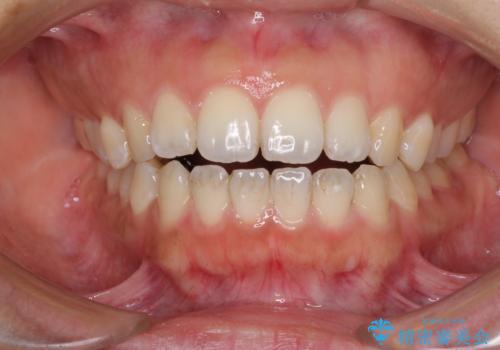

全く目立たないワイヤー矯正 上下リンガル矯正

- 上下の前歯のでこぼこを気にして来院された患者様です。

結婚式が近いこともあり、全く目立たない裏側矯正により口元を整えることとしました。

下顎が左側にずれているため、裏側矯正ということもあり咬み合わせを整えるのに時間がかかってしまいました。